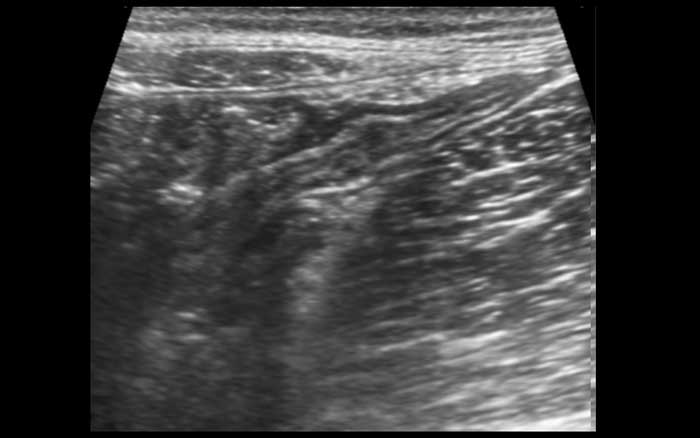

Đo độ dày thành ruột bằng siêu âm là khó khăn vì độ dày thay đổi theo các chuyển động nhu động ruột.

Ở cá nhân này, các số đo trong mặt phẳng dọc (hình trên) và trong mặt phẳng ngang khi ép nhẹ (hình dưới bên trái) có sự biến thiên đáng kể, nhưng khi ép vừa phải (hình dưới bên phải) các số đo có độ tái lập tốt và chính xác.

Vì lớp thanh mạc tăng âm mỏng hiếm khi có thể nhìn thấy rõ, độ dày thành ruột được đo từ bờ ngoài của lớp cơ mặt bụng đến bờ ngoài của lớp cơ mặt lưng, và sau đó tất nhiên, chia đôi.

Thông thường, độ dày thành ruột non đơn lớp khi ép là khoảng 1,5 – 2,5 mm.

Đo độ dày thành ruột bằng siêu âm theo cách này có tính tái lập và tương đương với những gì các phẫu thuật viên thực hiện bằng ngón tay trong quá trình mở bụng để xác định xem ruột non có bất thường hay không.

Ngược lại với hầu hết các quai ruột bệnh lý, các quai ruột non bình thường có thể bị ép xẹp tốt trong thì giãn nghỉ.